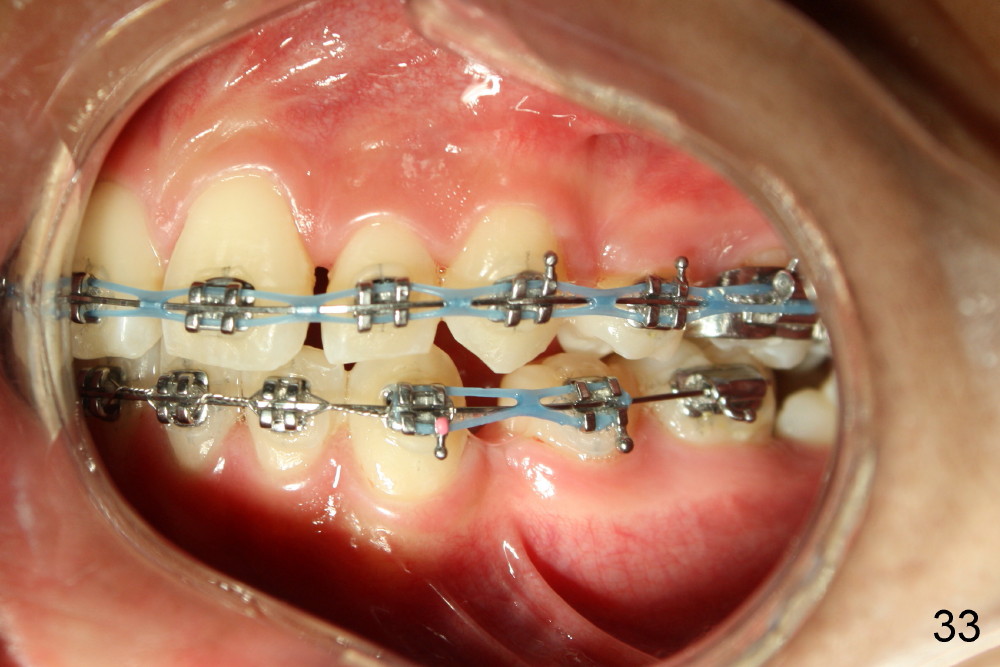

The kid returns 1 month 10 days after last visit. Wires change to 16x22 ss with figure-8 wires placed between UR3 and UL4 and between LL3 and LR 4 (Fig.41-45). A separator is placed between LL6 and 7.